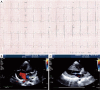

Figure 2

Atrial septal defect with left ventricular restriction. (A) Twelve-lead ECG of a 20-year-old with hypertrophic cardiomyopathy. (B) Transthoracic 2D echocardiography showing a moderate sized ASD. (C) Concentric left ventricular hypertrophy. ASD, atrial septal defect.